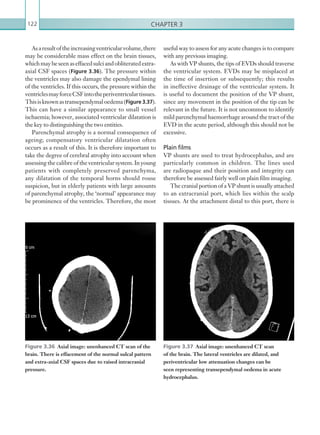

both the trauma team leader and the interventional

radiologist after consultation with other consultants

involved (Appendix 5). Decisions must be made

quickly and should be driven by agreed algorithms.

Establishing routes of communication between the

services is paramount.

Quality indicator

All imaging should be discussed at debriefing